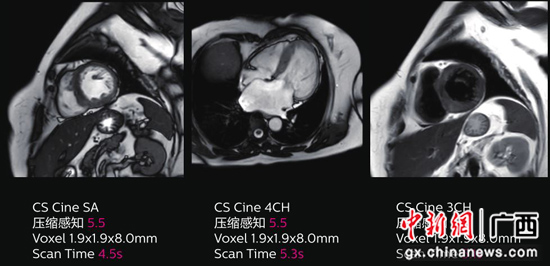

压缩感知心脏成像扫描时间缩短 53%,运动伪影少,屏气失败的概率更低。南溪山医院供图 Ingenia 3.0T CX磁共振在神经系统方面优势明显,可实现如128方向脑纤维束成像、脑小血管病变多模态成像、不打药臂丛神经成像等技术,它所配备的APT(酰氨质子转移)分子成像技术,通过探索蛋白质在体内的代谢转移来分析相关疾病,能评估肿瘤、脑卒中、老年病等重大疾病的蛋白质表达,既安全、又高效,这一分子成像技术为临床医生对肿瘤术前及术后病人选择合适的治疗方案提供了有利帮助。另外,它还可提供如骨关节系统的成分测量(T1 mapping)等定量分析,利用此项技术对骨关节方面的疾病研究等。在高分辨微米成像方面,该设备还配备有直径仅为23 mm/47 mm的数字化显微线圈,可精细显示如手指背侧韧带等细微结构。通过结合多通道颅脑线圈扫描可清晰显示脑内及颈部血管的管腔和管壁,内耳中面神经、蜗神经以及前庭上下神经等微小解剖结构的显示,有助于疑难疾病的诊断和辨别。